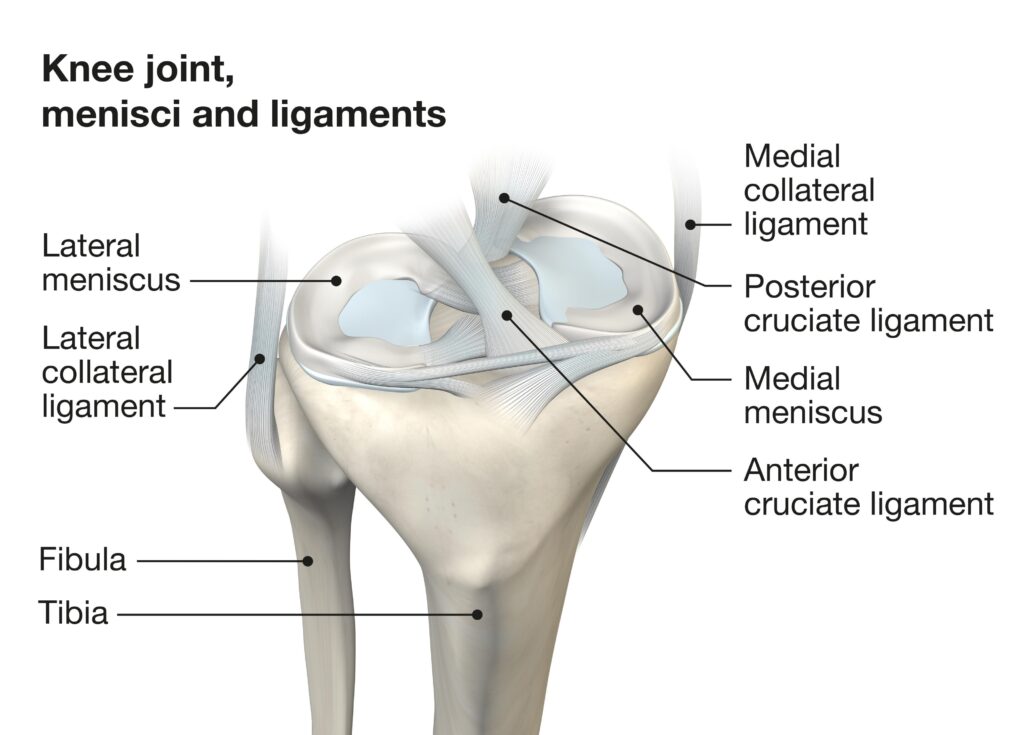

Image-1 -ACL

1 ACL (Anterior Cruciate Ligament)

What is ACL?

The Anterior Cruciate Ligament is one of the major ligaments inside the knee joint. It connects the femur (thigh bone) to the tibia (shin bone) at the center of the knee. It controls forward movement and rotational stability of the knee.

Function

- Prevents the tibia from moving forward excessively

- Provides rotational stability for twisting movements

- Essential for jumping, landing, pivoting and sudden direction change